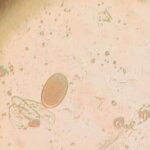

El pasado 25 de julio, en el laboratorio de la Facultad de Medicina Veterinaria, los alumnos del grupo 4AM llevaron a cabo la práctica de observación directa de heces para la detección de parásitos, correspondiente a la materia de Parasitología.

Durante la sesión, los estudiantes realizaron la toma de muestras y posteriormente la observación en microscopio de heces animales posiblemente parasitadas, reforzando así sus conocimientos teóricos con la experiencia práctica.